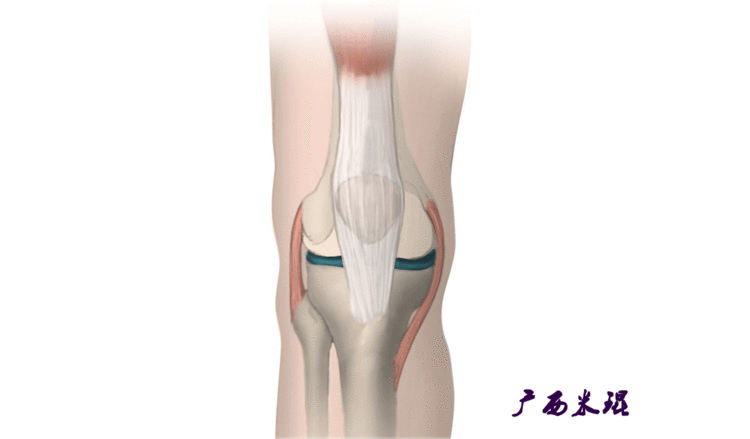

说到髌骨脱位,首先就要了解髌骨,髌骨是人体最大的籽骨,倒三角状位于膝关节前方,它的上缘与股四头肌腱相连,下缘通过髌韧带止于胫骨结节上,两侧为股四头肌扩张部,髌骨后方的凸面为光滑的关节面,与股骨下端内外髁之间的滑车凹面关节面形成关节。尽管股四头肌中的股直肌、股中间肌、股外侧肌的作用方向与髌韧带不在一条直线上,髌骨有向外突出的倾向,但因股内侧肌有向内上方牵拉作用力而使髌骨维持在正常位置。